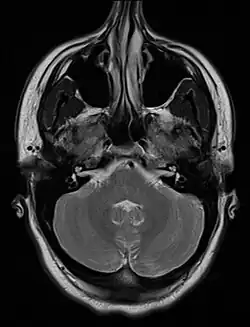

El tabique nasal es el hueso y el cartílago de la nariz que separa la cavidad nasal en las dos fosas nasales. El cartílago se llama cartílago cuadrangular y los huesos que comprenden el tabique incluye la cresta maxilar, vómer y la placa perpendicular del etmoides. Normalmente, el tabique se encuentra en el centro, y por lo tanto los conductos nasales son simétricos. Un tabique desviado es una condición anormal en la que la parte superior de la cresta cartilaginosa se inclina hacia la izquierda o la derecha, provocando la obstrucción del conducto nasal afectada. La condición puede resultar en un mal drenaje de los senos paranasales. Los pacientes también pueden quejarse de dificultad para respirar, dolores de cabeza, sangrado por la nariz, o de trastornos como los ronquidos o apnea del sueño.